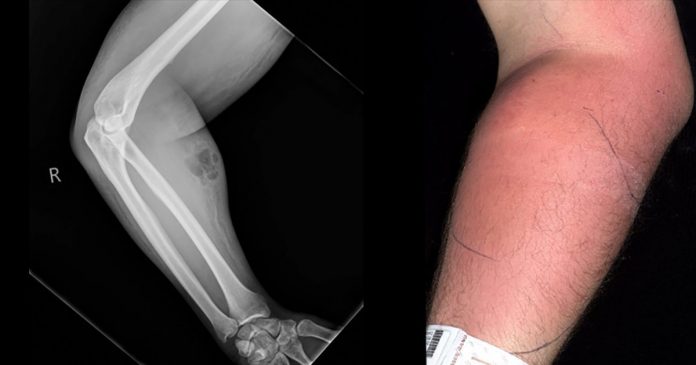

This ‘injecting semen’ habit of his turned into another health issue of severe swelling on his arm.

The doctors noticed the swelling on his arms and advised him to get an X-Ray done.

But he didn’t choose to get the semen removed at the hospital where it was brought to his notice that there is a need of the semen removal from his infected arm. The injecting of semen led to the problem of cellulitis; although he got much better with time despite his not so smart decision of not staying longer at the hospital.

The medical report prepared by Dr. Dunne mentioned that the man’s soft tissue got exposed to semen due to the leakage of semen in the tissue area.